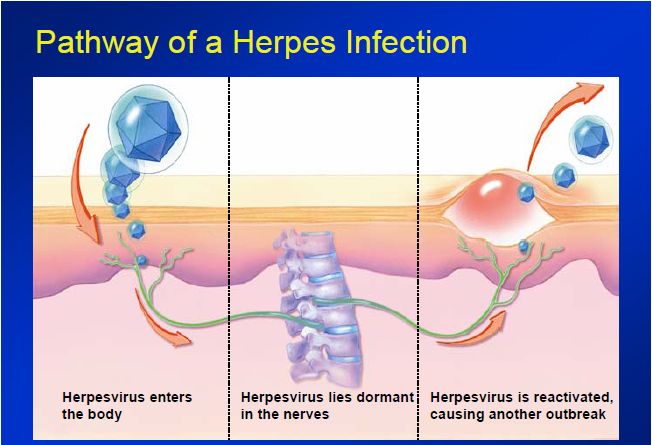

Медицинские снимки и изображения опоясывающего герпес вируса

Раздел: Фотодневник открытий